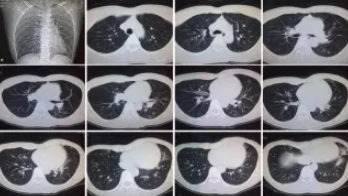

CT檢查原理是X光分層穿過人體,這就像把面包切成薄片,每一片都可以攤開看。當遇到外傷懷疑傷到骨頭,可以選擇CT觀察隱匿損傷或軟組織損傷。

CT適用于頭部、胸部、腹部、盆腔、脊柱、四肢、骨骼等處,由于它的特殊診斷價值,已經廣泛應用于臨床,特別是在腫瘤的診斷上更是具有很高的應用價值。但由于CT設備較為昂貴,檢查費用也會偏高,對于某些部位的檢查和診斷價值,尤其是定性診斷,還有一定限度,所以在臨床上并沒有將CT檢查視為常規診斷手段。此外,CT診斷輻射量大于DR,所以懷孕或備孕期女性不宜進行CT檢查。